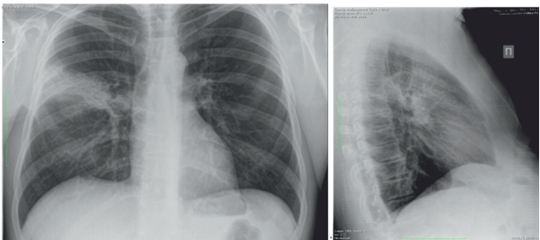

Пациент Е., 53 лет, в марте 2016 г. отметил повышение температуры до 39°C, появилась одышка при физической нагрузке, малопродуктивный кашель. Лечился самостоятельно (ингавирин, парацетамол). Через 10 дней обратился в поликлинику, выполнена рентгенография органов грудной клетки. На рентгенограмме: инфильтрация в верхней доле правого легкого (рис. 1). Пациент направлен на госпитализацию, отделение торакальной хирургии с диагнозом «внебольничная деструктивная пневмония верхней доли справа».

рис 1.